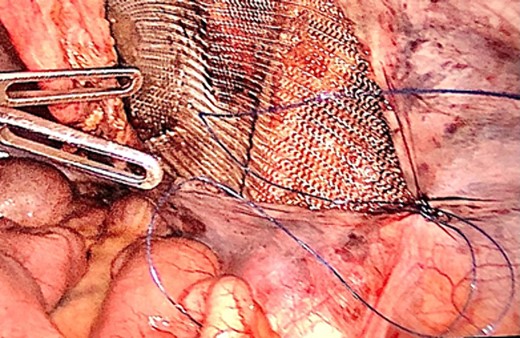

The hernia sac was found to invaginate the right inguinal ring, and after drawing back the hernia sac, the atrophic testis, along with the spermatic cord and testicular vessels, was revealed (Fig. 4). Heavyweight mesh was used (Fig. 5). The operative time was 95 min. No complications were noted and the patient was discharged on postoperative day 2. Pathological examination revealed no malignancy or spermatogenic abilities. No improvement in the semen analysis results was noted during the follow-up period. To date, there has been no recurrence of the hernia.

Laparoscopic view of the dissected testicle from the inguinal canal and the hernia sac associated.

Laparoscopic view of the peritoneal suture in the TAPP procedure performed after orchiectomy.